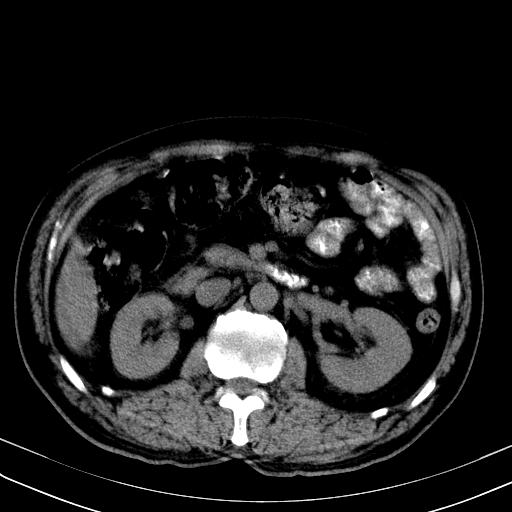

先行ct平扫,纵膈内多发软组织影,ct值约为36hu,以下为增强扫描和腹部平扫。

经典?纵膈多发肿大淋巴结。腹膜后未见异常。

还见胃窦壁增厚!转移亦有可能!

支持淋巴瘤

淋巴瘤可能

1)考虑淋巴瘤。2)双侧少量胸腔积液。